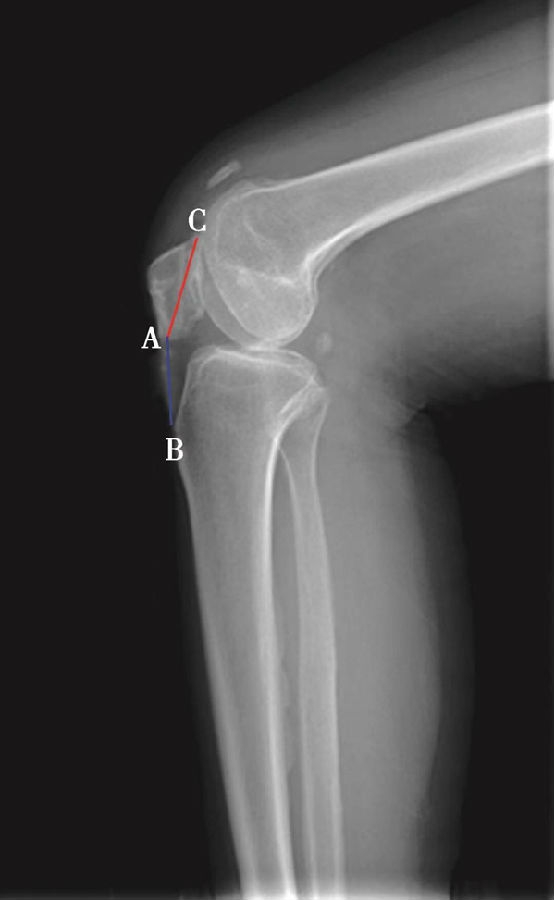

(2)Insall-Salvati指数>1.2意味着高位髌骨(图5),<0.8意味着低位髌骨(图6)。

如图示:AB是髌韧带长度,AC髌骨纵轴长度。Insall-Salvati指数=AB/AC(图4)。

图5 Insall-Salvati指数=AB/AC=1.40,为高位髌骨

但是此法测量髌骨韧带时往往依赖准确的估计胫骨结节与髌骨下极的位置。因此,髌骨下极和胫骨结节的病变都会影响测量的结果,尤其是发生胫骨结节骨软骨炎的患者确定这一位置便更加的困难。此外,该指数不能用于评估胫骨结节向近端或远端移位的效果。因为该指数测量所使用的标记在胫骨结节术后均未发生改变,Insall指数也就不会变化。